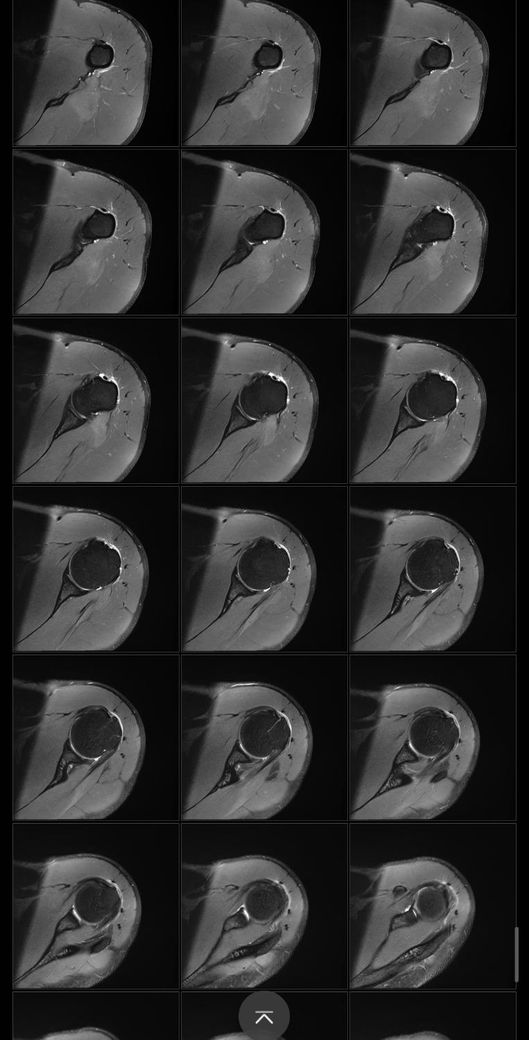

어깨 mri 전문의 소견 부탁드립니다

얼마전에 축구하다가 넘어지고 그날 저녁부터 팔이 안올라가서 건협가서 mri 찍었습니다.

회전근개 파열이 있는지, 없다면 지금 상태가 어떤상태인지와 웨이트 운동 가능할정도의 회복기간이 궁금합니다

Mri에서 별다른 이상소견이 없는 경우 일시적으로 발생하는 움직임이나 기능의 제한일 수 있습니다.

약 2주 이내의 회복기간이 소요될 수 있으며, 현재 mri 사진에서 보이는 염증 소견은 타박상으로 인해서 발생하는 것일 수 있습니다.

별다른 파열의 징후는 보이지 않습니다.

질문하신 내용 잘 읽어보았습니다. MRI결과에서 회전근개 파열 여부가 핵심입니다 부분 파열과 염좌라면 보존적 치료후 6~8주 내 웨이트 복귀 가능하지만 완전파열이면 수술 후 최소 3~6개월 재활이 필요합니다. mri 판독 결과지를 확인해야 정확한 상태와 회복 기간을 판단할 수 있습니다!